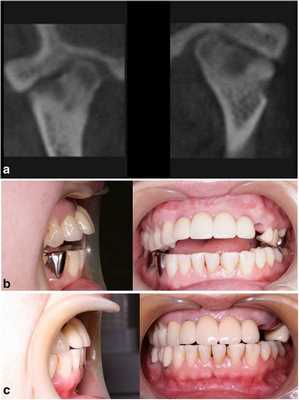

53-летняя женщина с ревматоидным артритом руки, запястья и плеча, обратилась за помощью по причине болевых ощущений в обоих ВНЧС. Она страдала от ревматоидного артрита в течение 1 года и принимала противовоспалительные препараты. КТ-диагностика подтвердила ревматоидное поражение обоих ВНЧС (фото 3а). У пациентки отмечалось ограниченное открывание полости рта (максимально до 23 мм), а болевые ощущения усиливались при движениях нижней челюсти. Для облегчения болевых симптомов было начато изготовление шины и проведен артроцентез обоих ВНЧС. Симптомы улучшились, однако у пациентки медленно начал развиваться передний прикус. Вертикальное перекрытие изменилось от начальных -6 мм до 0 мм (фото 3b).

Фото 3.

а) КТ-срезы, демонстрирующие сплющивание суставных головок, нерегулярность суставной поверхности и сужение суставных пространств.

b) Передний открытый прикус, который раздвинулся во время лечения с использованием шины.

с) Закрытие переднего открытого прикуса без прогрессирования нарушения в будущем.

Чтобы предотвратить прогрессирование патологии, была запланирована реконструкция ВНЧС. Во время операции было выполнено заднее перемещение верхней челюсти посредством остеотомии по Le Fort I, поскольку верхние передние зубы пациентки находились в состоянии протрузии. После резекции обоих мыщелков реконструкция ВНЧС с использованием протеза проводилась посредством вращения нижней челюсти против часовой стрелки для закрытия переднего открытого укуса (фото 3с). С момента операции на данный момент прошло уже 2 года, и в данный период не было отмечено никаких признаков воспалительного поражения области вмешательства. Симптомов прогрессирования открытого прикуса также не наблюдалось.